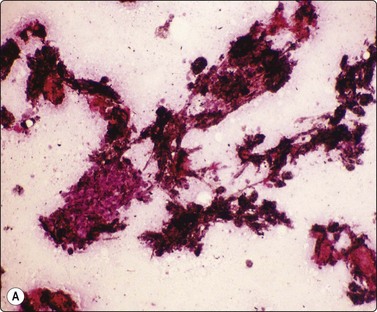

image image

Fig. 8.13 Anthraco-silicosis; progressive massive fibrosis

Bilateral upper zone/hilar lung masses in a miner. Dense masses of macrophages and fibrous tissue (A, H&E, MP; B, H&E, HP).